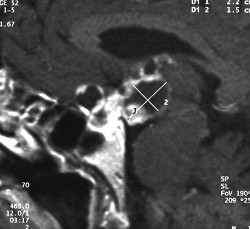

MRT eines intra- und suprasellären Kraniopharyngeoms mit dem typischen unregelmäßigen Aspekt. Man sieht gut die zentrale Lage im Bereich der Hypophyse und des Sehapparates

Die bildgebenden Verfahren der Wahl sind beim Kraniopharyngeom die Kernspintomografie (auch Magnetresonanztomografie oder MRT) und die Computertomographie (CT). Ferner sind meist eine gründliche Augenärztliche Untersuchung, eine komplette Hormonkontrolle sowie neuro-psychologische Tests notwendig.